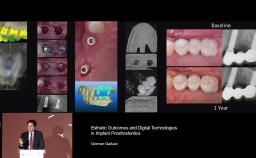

Dr. Gallucci is the Chair of the Department of Restorative and Biomaterial Siences at Harvard School of Dental Medicine. ITI Fellow since 2004, Chair of the ITI Scholarship Center at Harvard.

Academy content by German Gallucci (42 items)